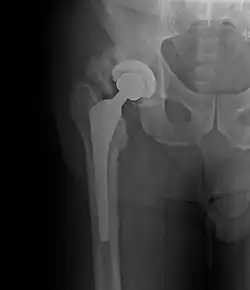

Osificación heterotópica

La osificación heterotópica (HO) es el crecimiento de hueso en lugares anormales, como en tejido blando. Esto puede ocurrir en cualquier parte del cuerpo; la cadera, rodillas, hombros y codos son los lugares más comunes. Esta condición puede variar de crecimiento menor a fuerte.

- Cirugía en la cadera u otra cirugía en articulaciones

- Rayos X - podrían solo detectar hueso anormal en fases posteriores de la enfermedad

Cirugía

Podría usarse cirugía para retirar el hueso anormal e incrementar el rango de movimiento.